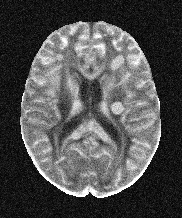

Refer to caption

(a) b = 0 s/mm2

(b) b = 300 s/mm2

(c) b = 1000 s/mm2

Figure 2: Example axial slice from the clinical brain dMRI, involving b-values of 0, 300 and 1000 s/mm2.

Three orthogonal (x, y, z) diffusion directions were sampled at b-values of 0, 300 and 1000 s/mm2. The images have spatial resolution of 1.4×\times×1.4×\times×5 mm3. For the sake of denoising quality evaluation, the number of scan repetitions was set to the maximum possible value of 32. The images were exported as raw data and reconstructed using the algorithm described in [10, Section 3.1]. An example slice at all b-values is shown in Figure 2.